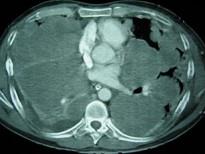

问题 33岁,男,咳嗽1周,有骨肉瘤病史,请结合胸片和CT图,选出最可能的诊断 ( )

选项 A.肺梗死 B.粟粒性肺结核 C.骨肉瘤转移 D.结节病 E.错构瘤

答案 C